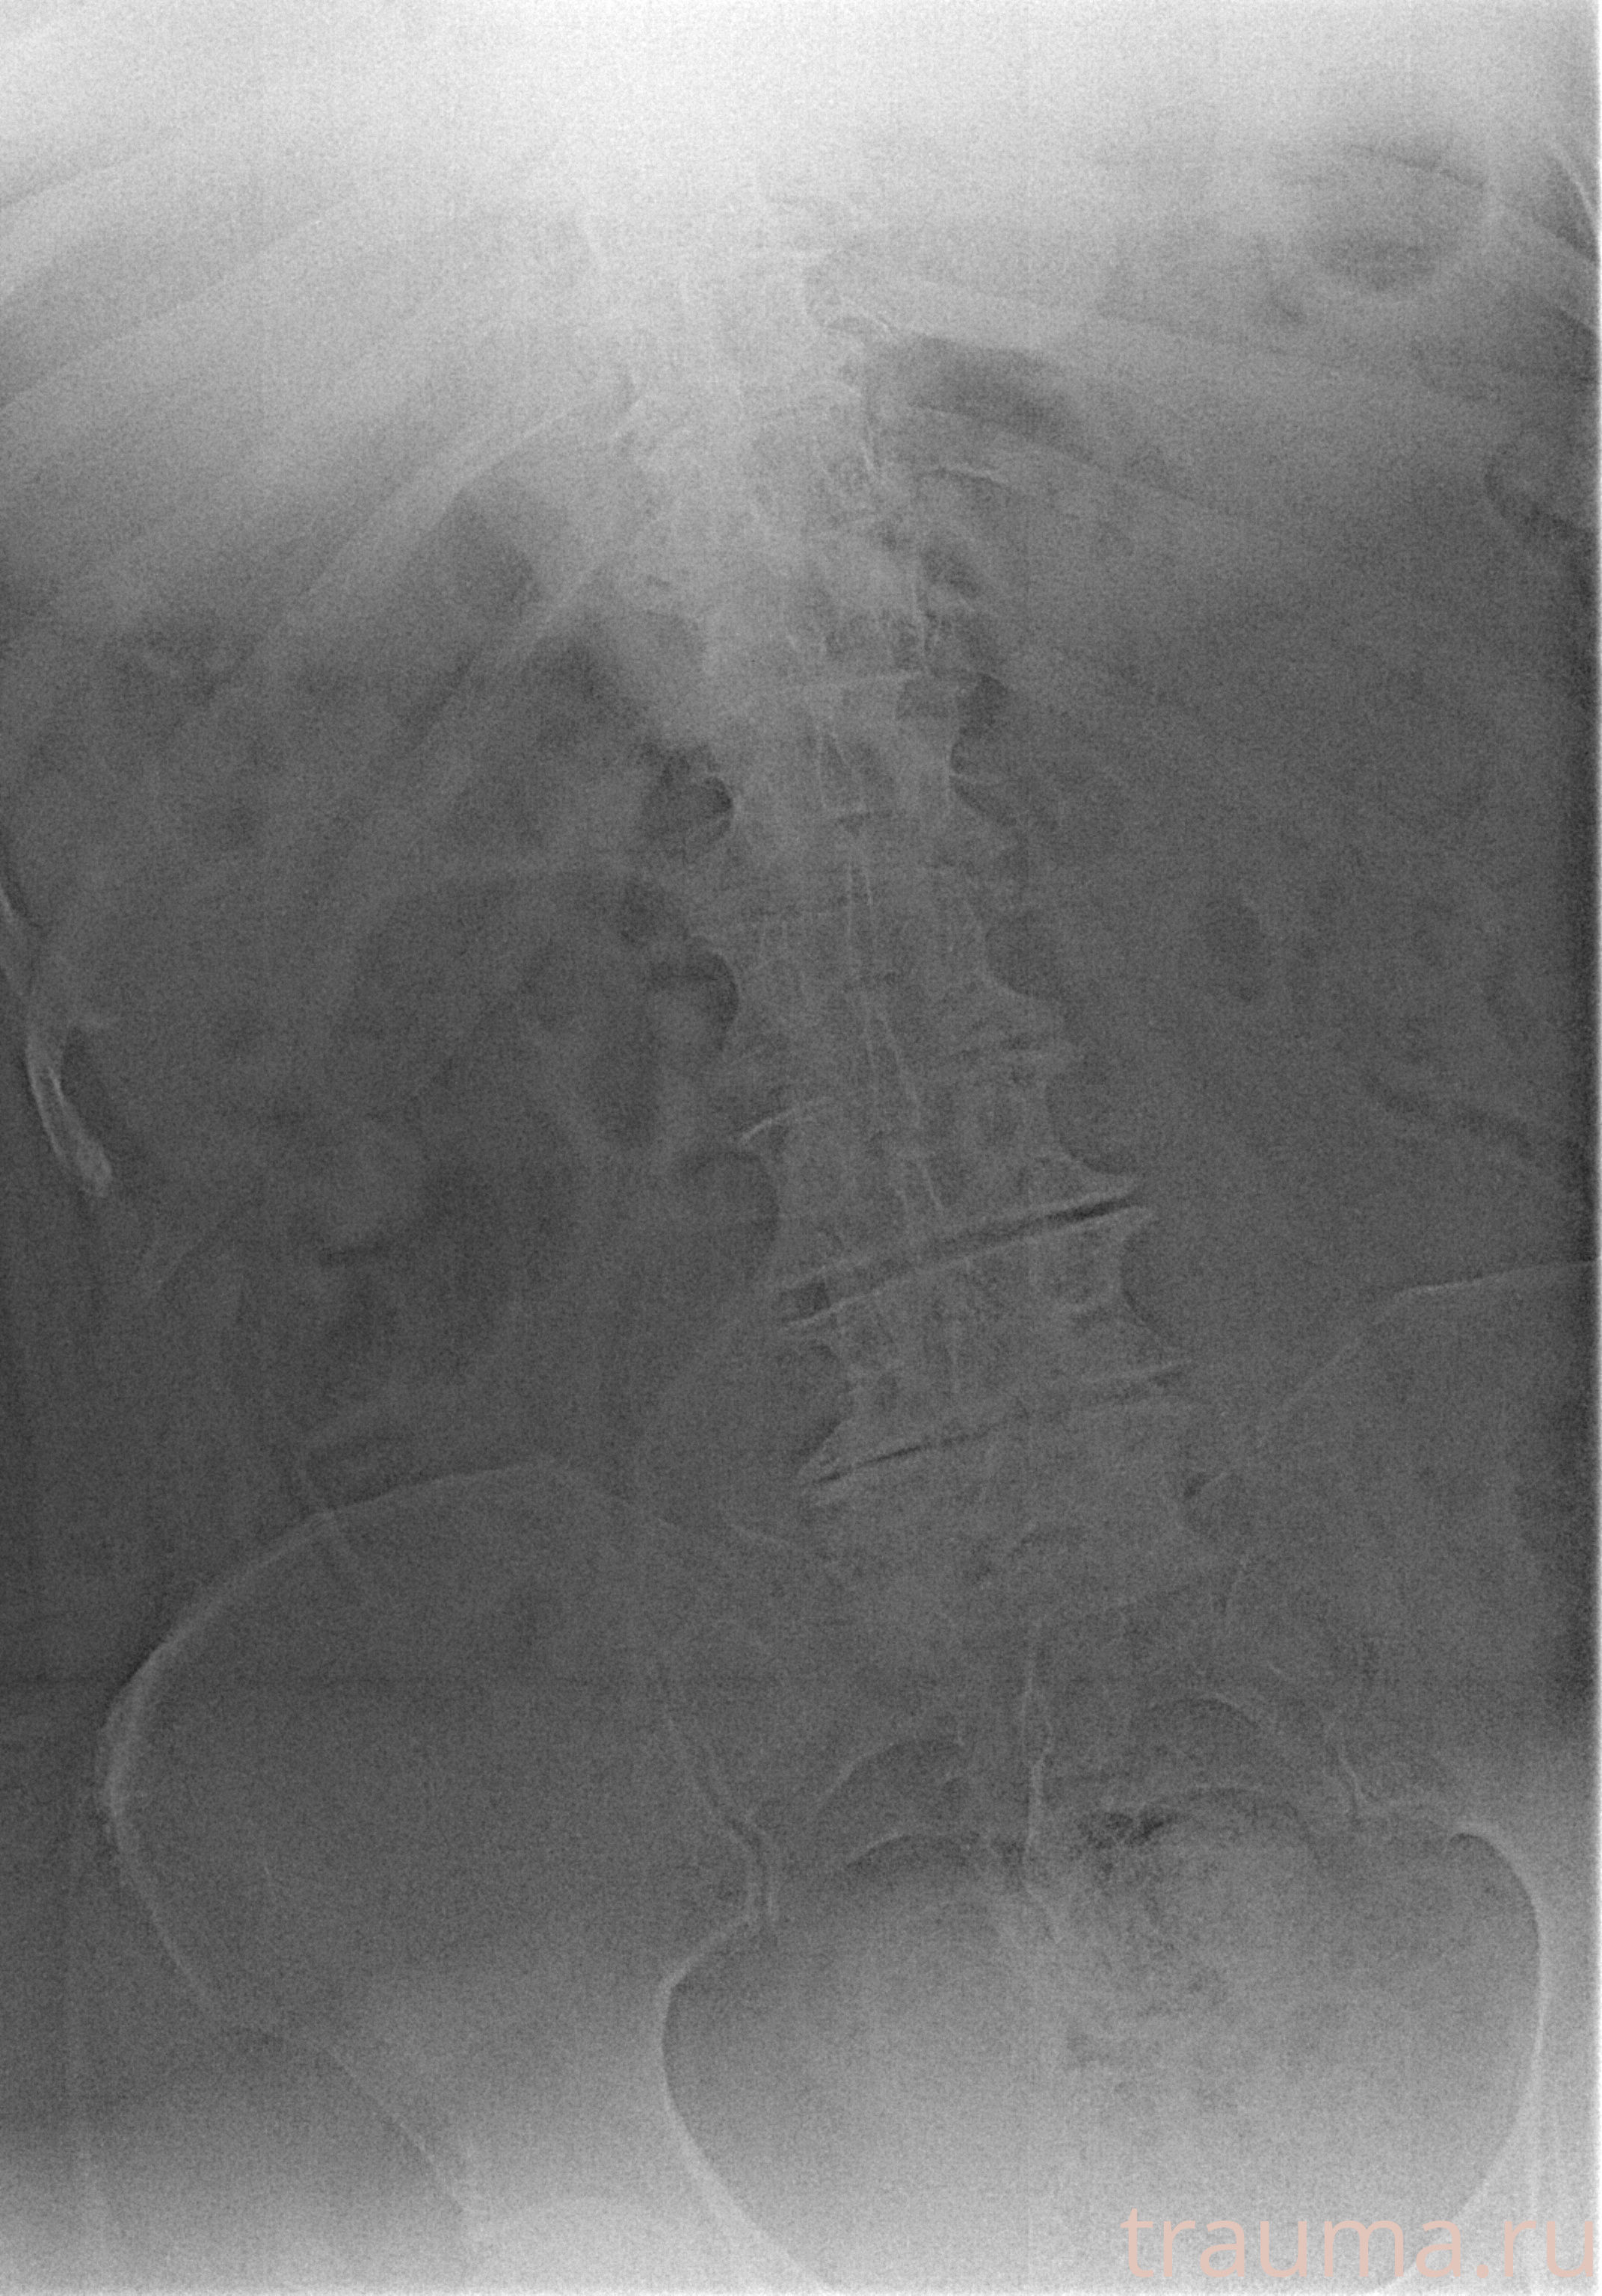

Рентгенограммы

Рентген на дому: по вашему адресу приезжает врач-рентгенолог, травматолог-ортопед с мобильным рентгеновским аппаратом, проводит диагностику травмы или заболевания, делает необходимые рентгенограммы, дает рекомендации по дальнейшему лечению. Получить качественные снимки в домашних условиях возможно благодаря уникальной методике, разработанной МосРентген Центром для института  Склифосовского